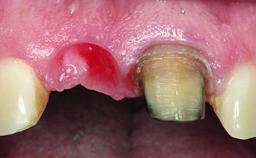

Loading Protocol Immediate

Provisional Implant-Supported Prosthesis Prosthodontic margin < 3 mm apical to mucosal margin Prosthodontic margin < 3 mm apical to mucosal margin

Soft Tissue Contour and Volume Ideal